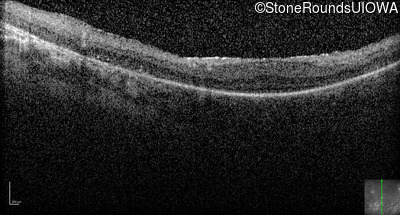

Optical Coherence Tomography - Right -

No Light Perception

Exemplar

Expanded OCT Stack

×